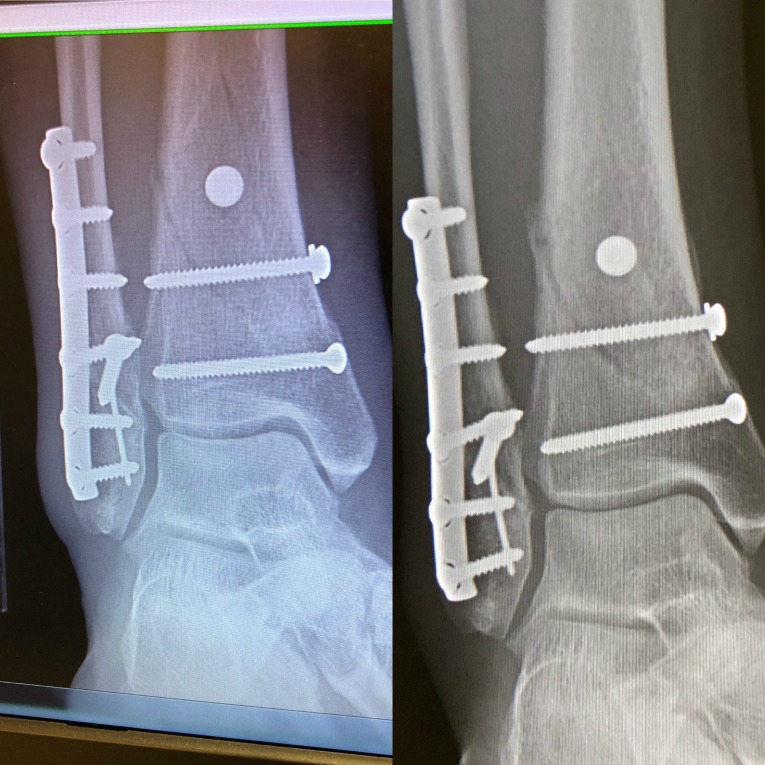

However, it was odd as my x-rays actually look worse in my opinion from just 1.5 months ago (left picture is in April, right picture is June).

Yet the surgeon explained that when the new bone growth comes in, it often looks like the gap of the break is widening, even though it is actually healing. And the little bubble on the side of the break is new bone growth and is a really good sign.

It’s still pretty crazy to see just how bad the break was (well, there were three breaks, but the one you can see clearly above was the most traumatic.)